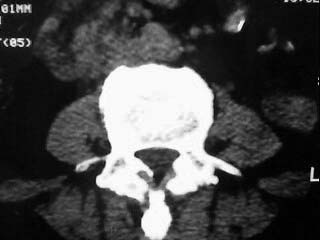

f,64。腰痛,腿麻三个月

是黄韧带钙化吗

腰椎退行性变;黄韧带钙化。

黄韧带增厚钙化